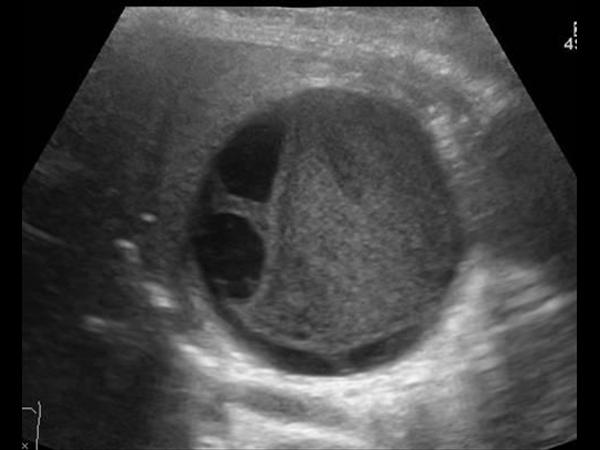

Chảy máu túi mật

Chảy máu túi mật - Ảnh 2

» Thông tin: Nữ giới – 81 tuổi.

» Lâm sàng: Đau mạn sườn phải / Sau thủ thuật ERCP.